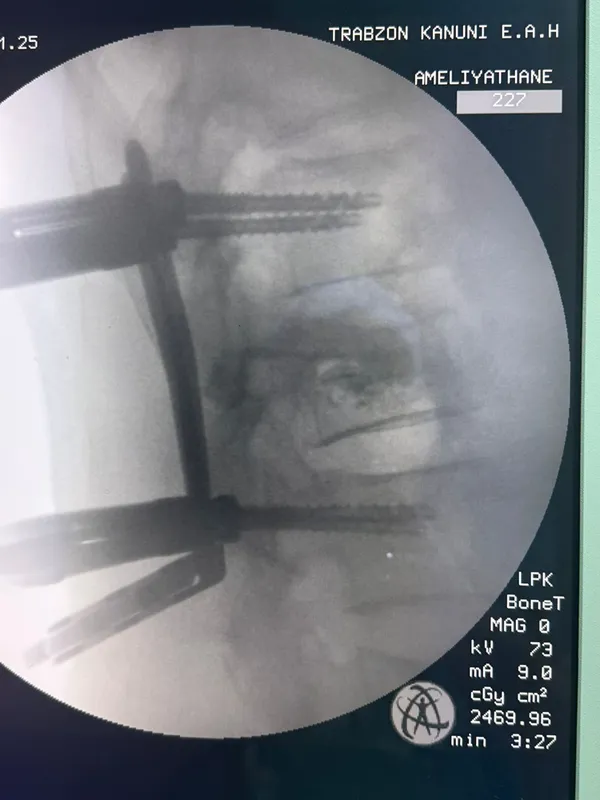

Trabzon'da omurga vidalama ameliyatı geçiren hasta sağlığına kavuştu

TRABZON (AA) - Kanuni Eğitim ve Araştırma Hastanesi'nde omurga vidalama ameliyatı geçiren hasta sağlığına kavuştu.

Hastaneden yapılan açıklamada, ameliyatta kullanılan cerrahi yöntem sayesinde hastaların daha hızlı iyileşme imkanı sağlandığı belirtildi.

Ameliyatı gerçekleştiren Beyin ve Sinir Cerrahisi Uzmanı Dr. Gürkan Uzun ise ameliyat ile hastadaki dokuya en az zararın verilerek tedavinin mümkün hale geldiğini vurguladı.

Uzun, kesi bölgesinin çok küçük olması nedeniyle ağrı, enfeksiyon ve iyileşme gibi konularda belirgin bir avantaj sağlandığına işaret ederek, operasyon sonrası hastanın kısa sürede günlük yaşantısına dönebildiğini kaydetti.